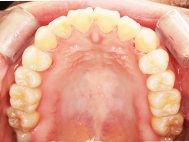

After

| 症状 | 上下前歯叢生 |

| 治療内容 | 上顎部分裏側矯正 下顎は目立ちにくい透明な装置 |

| 治療期間 | 11ヶ月 |

左上の前歯内側に入っている下の前歯ガチャ歯

左上前歯が下の歯の内側に入っているのが気になるとの事で来院されました。目立たない矯正治療を希望しているとのこでした。 上顎の装置は、歯の裏側(リンガル装置)で下顎は表側で矯正治療を行いました。口を閉じた時、上の前歯が内側に入っている為に下の歯を前に押し出している状態でした。その為、上の歯を前に出すだけではその歯が下とのかみ合わせの関係で、前に飛び出すような治療となってしまいます。 今回の症例ではシュミレーションを見て頂き、下の歯も治療し、内側へ下げることによって上の歯も飛びだすことなく、キレイにおさまることを説明し、上下一緒に矯正することをお勧めさせて頂きました。